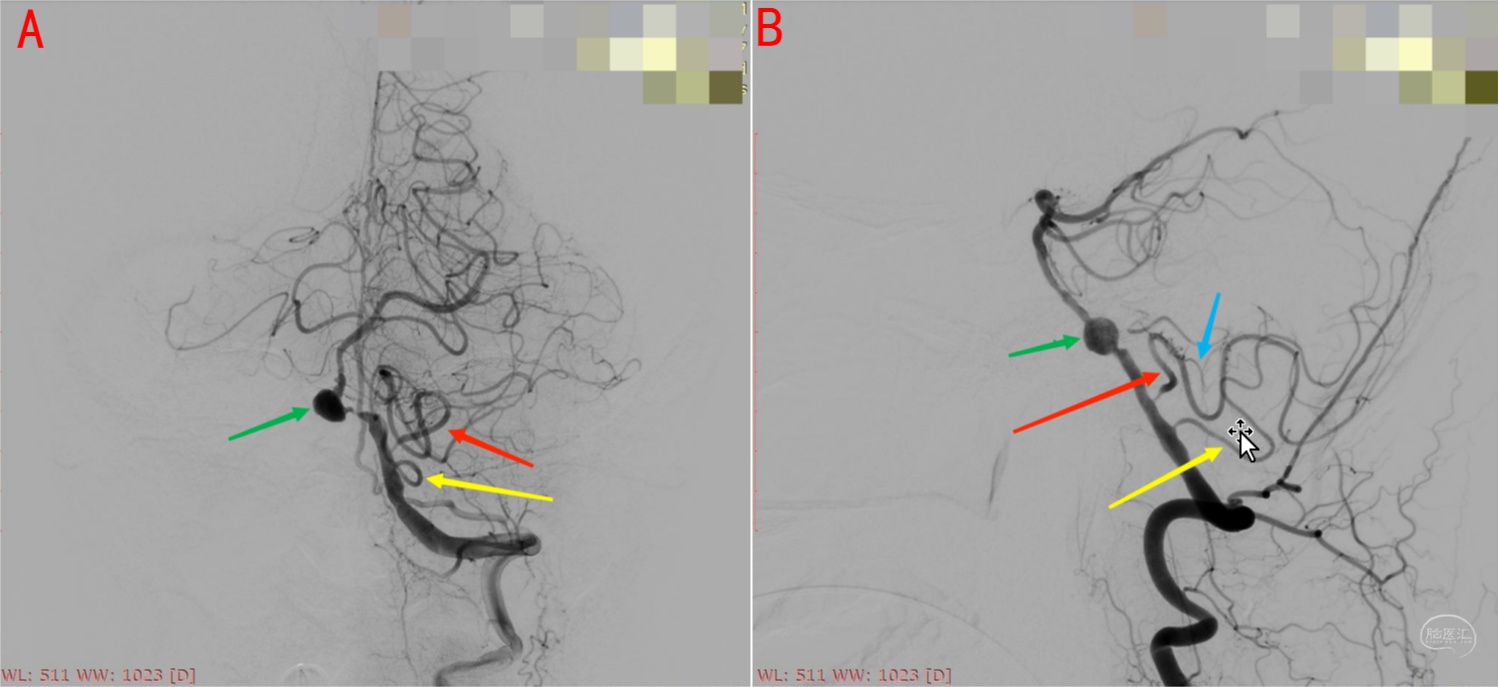

图9 正常小脑后下动脉DSA图像解读。图A为正位,图B为侧位,显示小脑后下动脉尾襻、颅襻、内侧干(蚓部供血)和外侧干(小脑半球枕下面供血)。延髓穿支一般发自于尾襻附近及其近端部位。

图10 小脑后下动脉双干变异。椎基底动脉汇合部动脉瘤(绿箭)合并左侧椎动脉V4段远端狭窄患者,左侧小脑后下动脉呈双干自V4段发出,黄箭所示下干远端主要向蚓部供血,红箭所示上干远端主要向小脑半球枕下面供血,尾襻近端发出延髓穿支(蓝箭)。